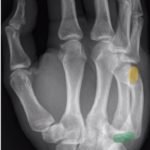

A two-view radiograph of the right hand was obtained which revealed a dorsal dislocation of the distal fourth and fifth metacarpals (see red and blue outline, respectively) with a concomitant fracture of the distal fifth metacarpal (see yellow line) and avulsion fracture of the lateral aspect of the hamate (see green line). After reduction the fourth and fifth metacarpal dislocations are resolved; however, the distal fifth metacarpal fracture (yellow line) and avulsion fracture of the lateral aspect of the hamate (green line) are still visible.